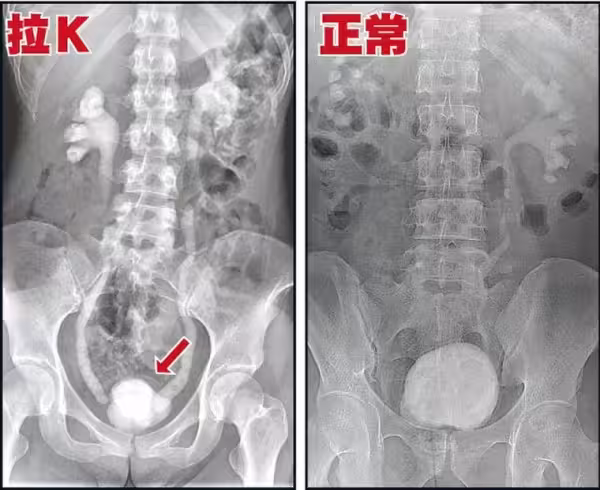

其實吸食K他命長久的人,必然會有這種尿頻、尿急、尿痛的症狀,

這是由於K他命的獨特性,持續傷害人體的泌尿系統,導致的嚴重後果。

K他命是一種結晶、有稜角的固體物質,

從鼻子吸入,然後進入呼吸系統、消化系統,

其中約有5%的K他命原型會經泌尿系統的尿道排出。